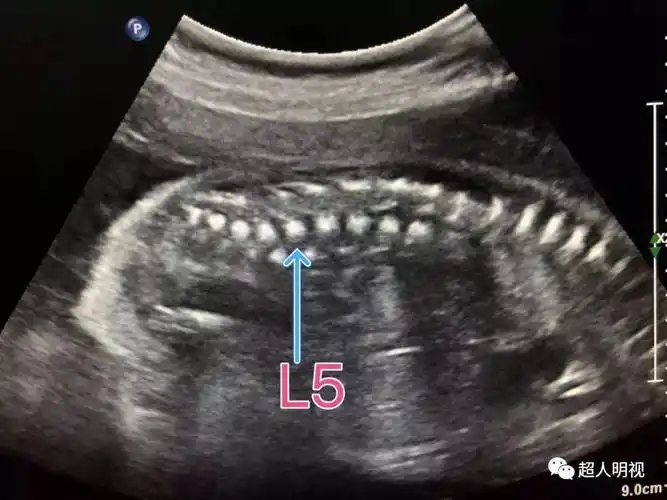

再谈胎儿脊髓圆锥几种定位法